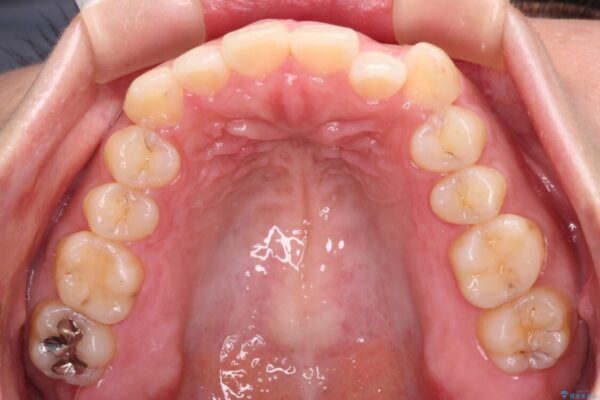

治療後

• 【モニター】カリエール・ディスタライザーを併用した八重歯のインビザライン矯正 治療後画像